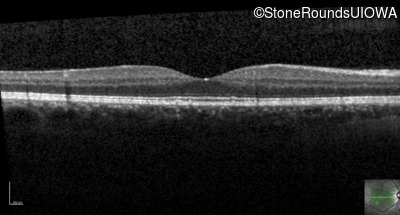

Optical Coherence Tomography - Right - 20/20 +1 sc

Exemplar / OCT Stack